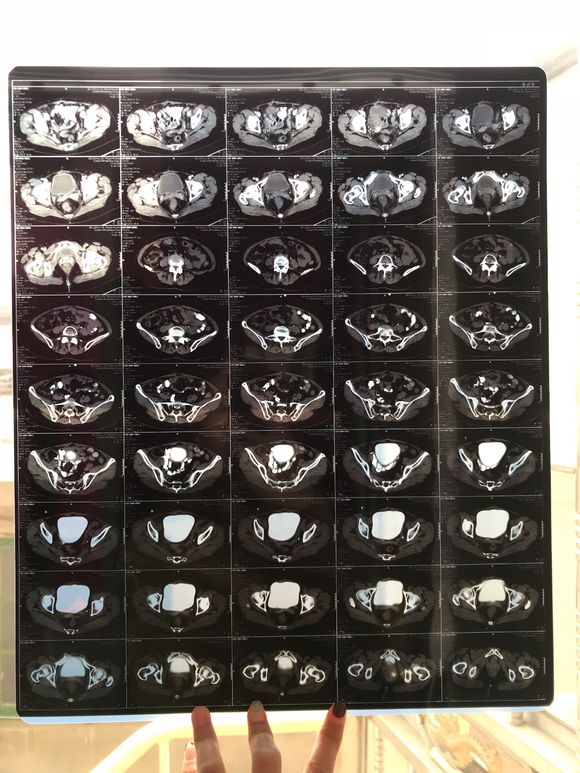

和你的故事 02019-04-09 患者家属我妈妈的病理结果报告,3期c1,大家可以帮忙看看吗,跪求了!我很急,谢谢!想知道是否严重,目前等术后出院后去肿瘤医院...

0人关注 4个回复 3466次浏览 -